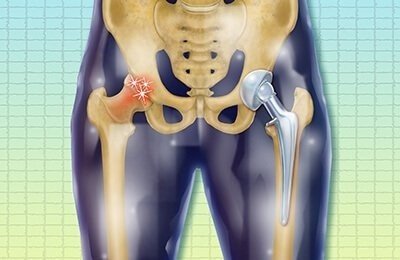

Hip replacement surgery involves replacing a damaged or worn-out hip joint with an artificial implant. This procedure is commonly recommended for patients suffering from severe joint pain or stiffness that does not respond to non-surgical treatments.

Patients visiting the Best Hospital for Hip Replacement in Gurugram Sector 52 often experience conditions such as osteoarthritis, rheumatoid arthritis, or hip fractures. The goal of the surgery is to relieve pain, restore movement, and improve overall quality of life.

Modern hip replacement procedures are designed to provide long-lasting results while minimizing discomfort and recovery time.